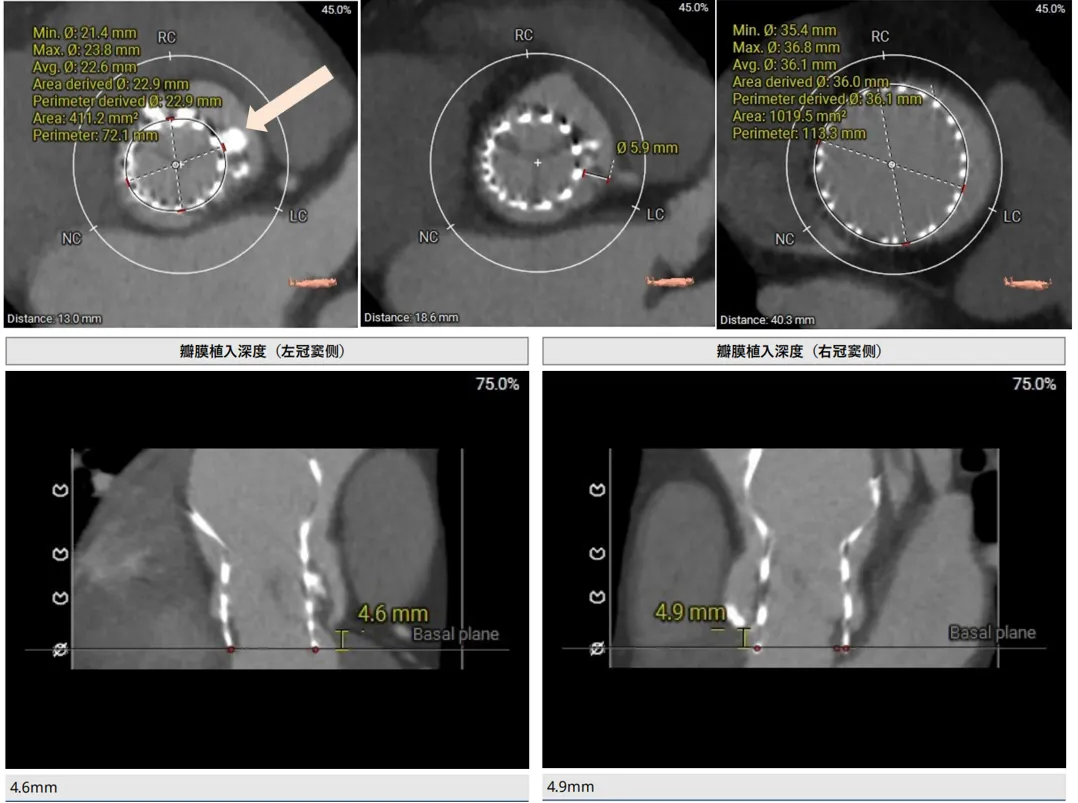

再来看一例三叶瓣的重度钙化对瓣膜的推挤,病例-4

遇见这种三叶瓣,边缘都有很重钙化的你会怎么画呢?瓣叶能推开么?要不要把边缘占满?这里考验的就是对钙化程度的综合理解了。刚刚也说了,瓣叶中间的钙化一般是可以推动的,除非连上了基底部有一大块的。而边缘的钙化,瓣膜往往没法占满。这就是钙化导致的瓣周漏的原因。

让我们来看看术前和术后预测的对比,预留的交界区域完全正确,瓣膜无法填满三个瓣叶的交界边缘,从瓣环到瓣上12mm都留有一丝缝隙,这类病例除非充分后扩贴一贴,不然多少都会有一点儿漏,术前可以充分预估到。

看大小:对你画的圈大概在那个位置心里有数以后,就涉及到圈画多大了,这里我都是一个原则,就是我画圈是为了看限制区域有多大,然后根据限制区域来看我的oversize值。除非看冠脉风险我才会根据瓣膜的参数,预估的植入位置来算这个平面的SIMU大小。